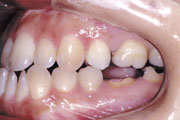

症例4:上顎前突